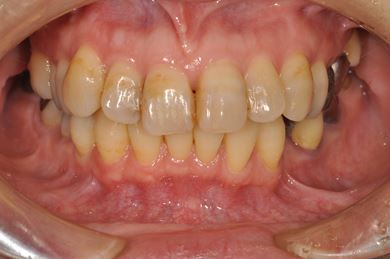

| 性別/年齢 | 女性 / 54歳 | ||||||||||||||||||||||||||||||||

| 主訴 | 下顎の奥歯を抜歯したままになっており、歯茎が少しやせて、両側の歯が少し倒れているような気がする。可能であればインプラントを入れたい。 | ||||||||||||||||||||||||||||||||

| 治療内容 | インプラント1本、メタルボンドセラミック1本 | ||||||||||||||||||||||||||||||||